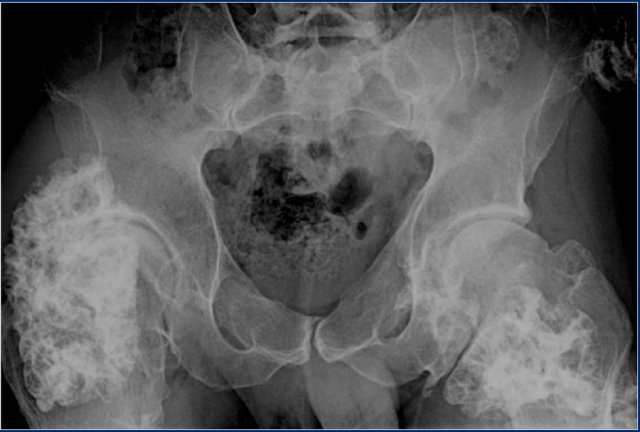

Here a patient with both sclerotic and osteolytic metastases.

It is a male patient, so your first thought is prostate cancer, which this patient had.